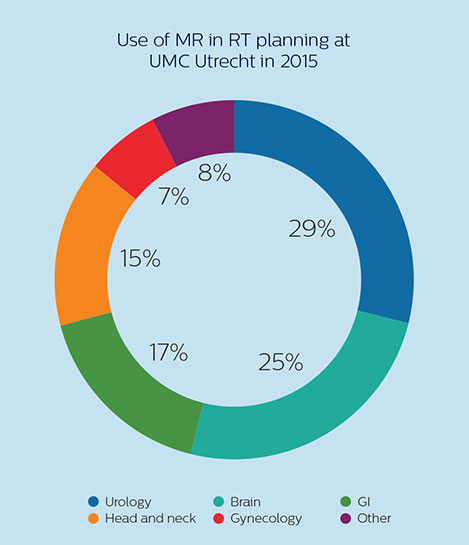

MRI is used for planning in a variety of anatomies

At UMC Utrecht, Dr. Philippens and her colleagues are using MRI in planning external beam radiation therapy (EBRT) for treatment of tumors in a variety of anatomies, such as organs in the pelvis (including bladder, prostate, rectum and cervix), the brain, the esophagus, pancreas, the larynx and oropharynx, bone metastases and sarcomas. In addition, MRI is also used to guide brachytherapy in the prostate and cervix. [6]

The University Medical Center Utrecht Department of Radiotherapy is a leading center in radiation therapy, continuously striving to improve methods and provide excellent patient care. UMC Utrecht has two Philips Ingenia MR-RT systems (1.5T and 3.0T) for RT treatment simulation as well as a Philips Ingenia 1.5T system dedicated for brachytherapy. Furthermore, it is an Atlantic MR-Linac consortium member.